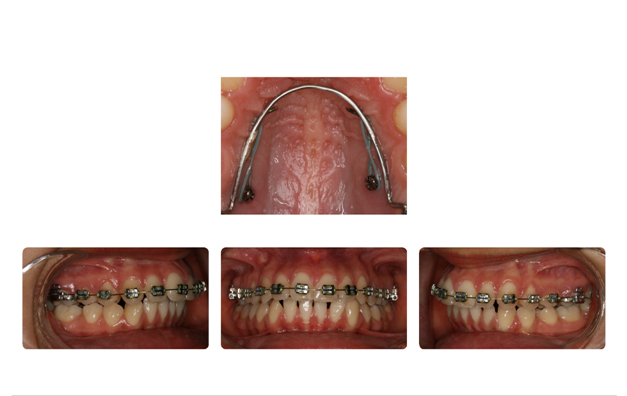

| دندان نهفته ی نیش سمت راست در قسمت کام وسمت چپ در زیر لب و بالای دندانها قرار دارد که توسط جراح لثه روی آن برداشته شده وتوسط ارتودنسی و براکتها به جای برده می شود: |

![]() |

| بعد از قرارگیری دندانها در جای خود ومرتب شدن آنها فک نیز آماده جراحی میباشد: |